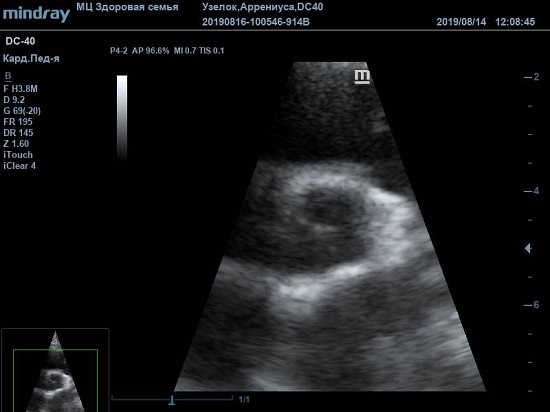

Найти их очень просто, достаточно сечений LAXLV (длинная ось) и SAXBASE (короткая ось). Специфические крупные шаровидные структуры – узелки Аррениуса - на кончиках полулуний клапана обнаружил ультразвуковой прибор

Mindray DC-40. В цветовом допплере без труда определяется аортальная регургитация легкой степени. Оценить её можно в CFM по соотношению JW/LVOT.